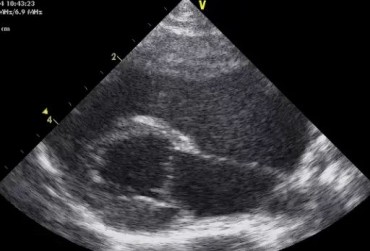

Dysplazja zastawki trójdzielnej i zespół Wolffa–Parkinsona–White’a u kota – opis przypadku

Zwężenie zastawki trójdzielnej jest jedną z form dysplazji pojawiającą się w różnym stopniu nasilenia (najczęściej łącznie z niedomykalnością zastawki) zarówno u psów, jak i u kotów. Cechami charakterystycznymi definiującymi zwężenie zastawki trójdzielnej są: obecność rozkurczowego wybrzuszenia (doming) płatków zastawki, zmniejszona ruchomość płatków, zmniejszona średnica ujścia zastawki. Mimo że zmiany morfologiczne aparatu trójdzielnego są typowe w przebiegu TVD i są znakiem rozpoznawczym tej choroby, nie są one zawsze bardzo silnie wyrażone i nie zawsze można mieć bezsprzeczną pewność diagnostyczną, bazując na badaniu echokardiograficznym [10]. Przypadki takie zdarzają się przede wszystkim u pacjentów, u których nie postawiono diagnozy we wczesnym etapie życia, a którzy pojawiają się na badaniu dopiero w starszym wieku z zaawansowanymi zmianami i niejednokrotnie z klinicznymi objawami prawostronnej niewydolności mięśnia sercowego i towarzyszącymi zaburzeniami w rytmie. W takich przypadkach obraz choroby może przypominać arytmogenną kardiomiopatię prawokomorową (arrhythmogenic right ventricular cardiomyopathy – ARVC) [1, 8]. Preekscytacja jest często obserwowana u ludzi z anomalią Ebsteina. U zwierzat, podobnie jak u ludzi, obecność dodatkowej drogi przewodzenia może nigdy nie prowadzić do rozwoju tachykardii nadkomorowej lub arytmia ta pojawiać się może dopiero w późniejszym okresie życia. Opisany przypadek jest przykładem pacjenta z dysplazją zastawki trójdzielnej i prawostronną niewydolnością serca będącą najprawdopodobniej konsekwencją tachykardii nadkomorowej.